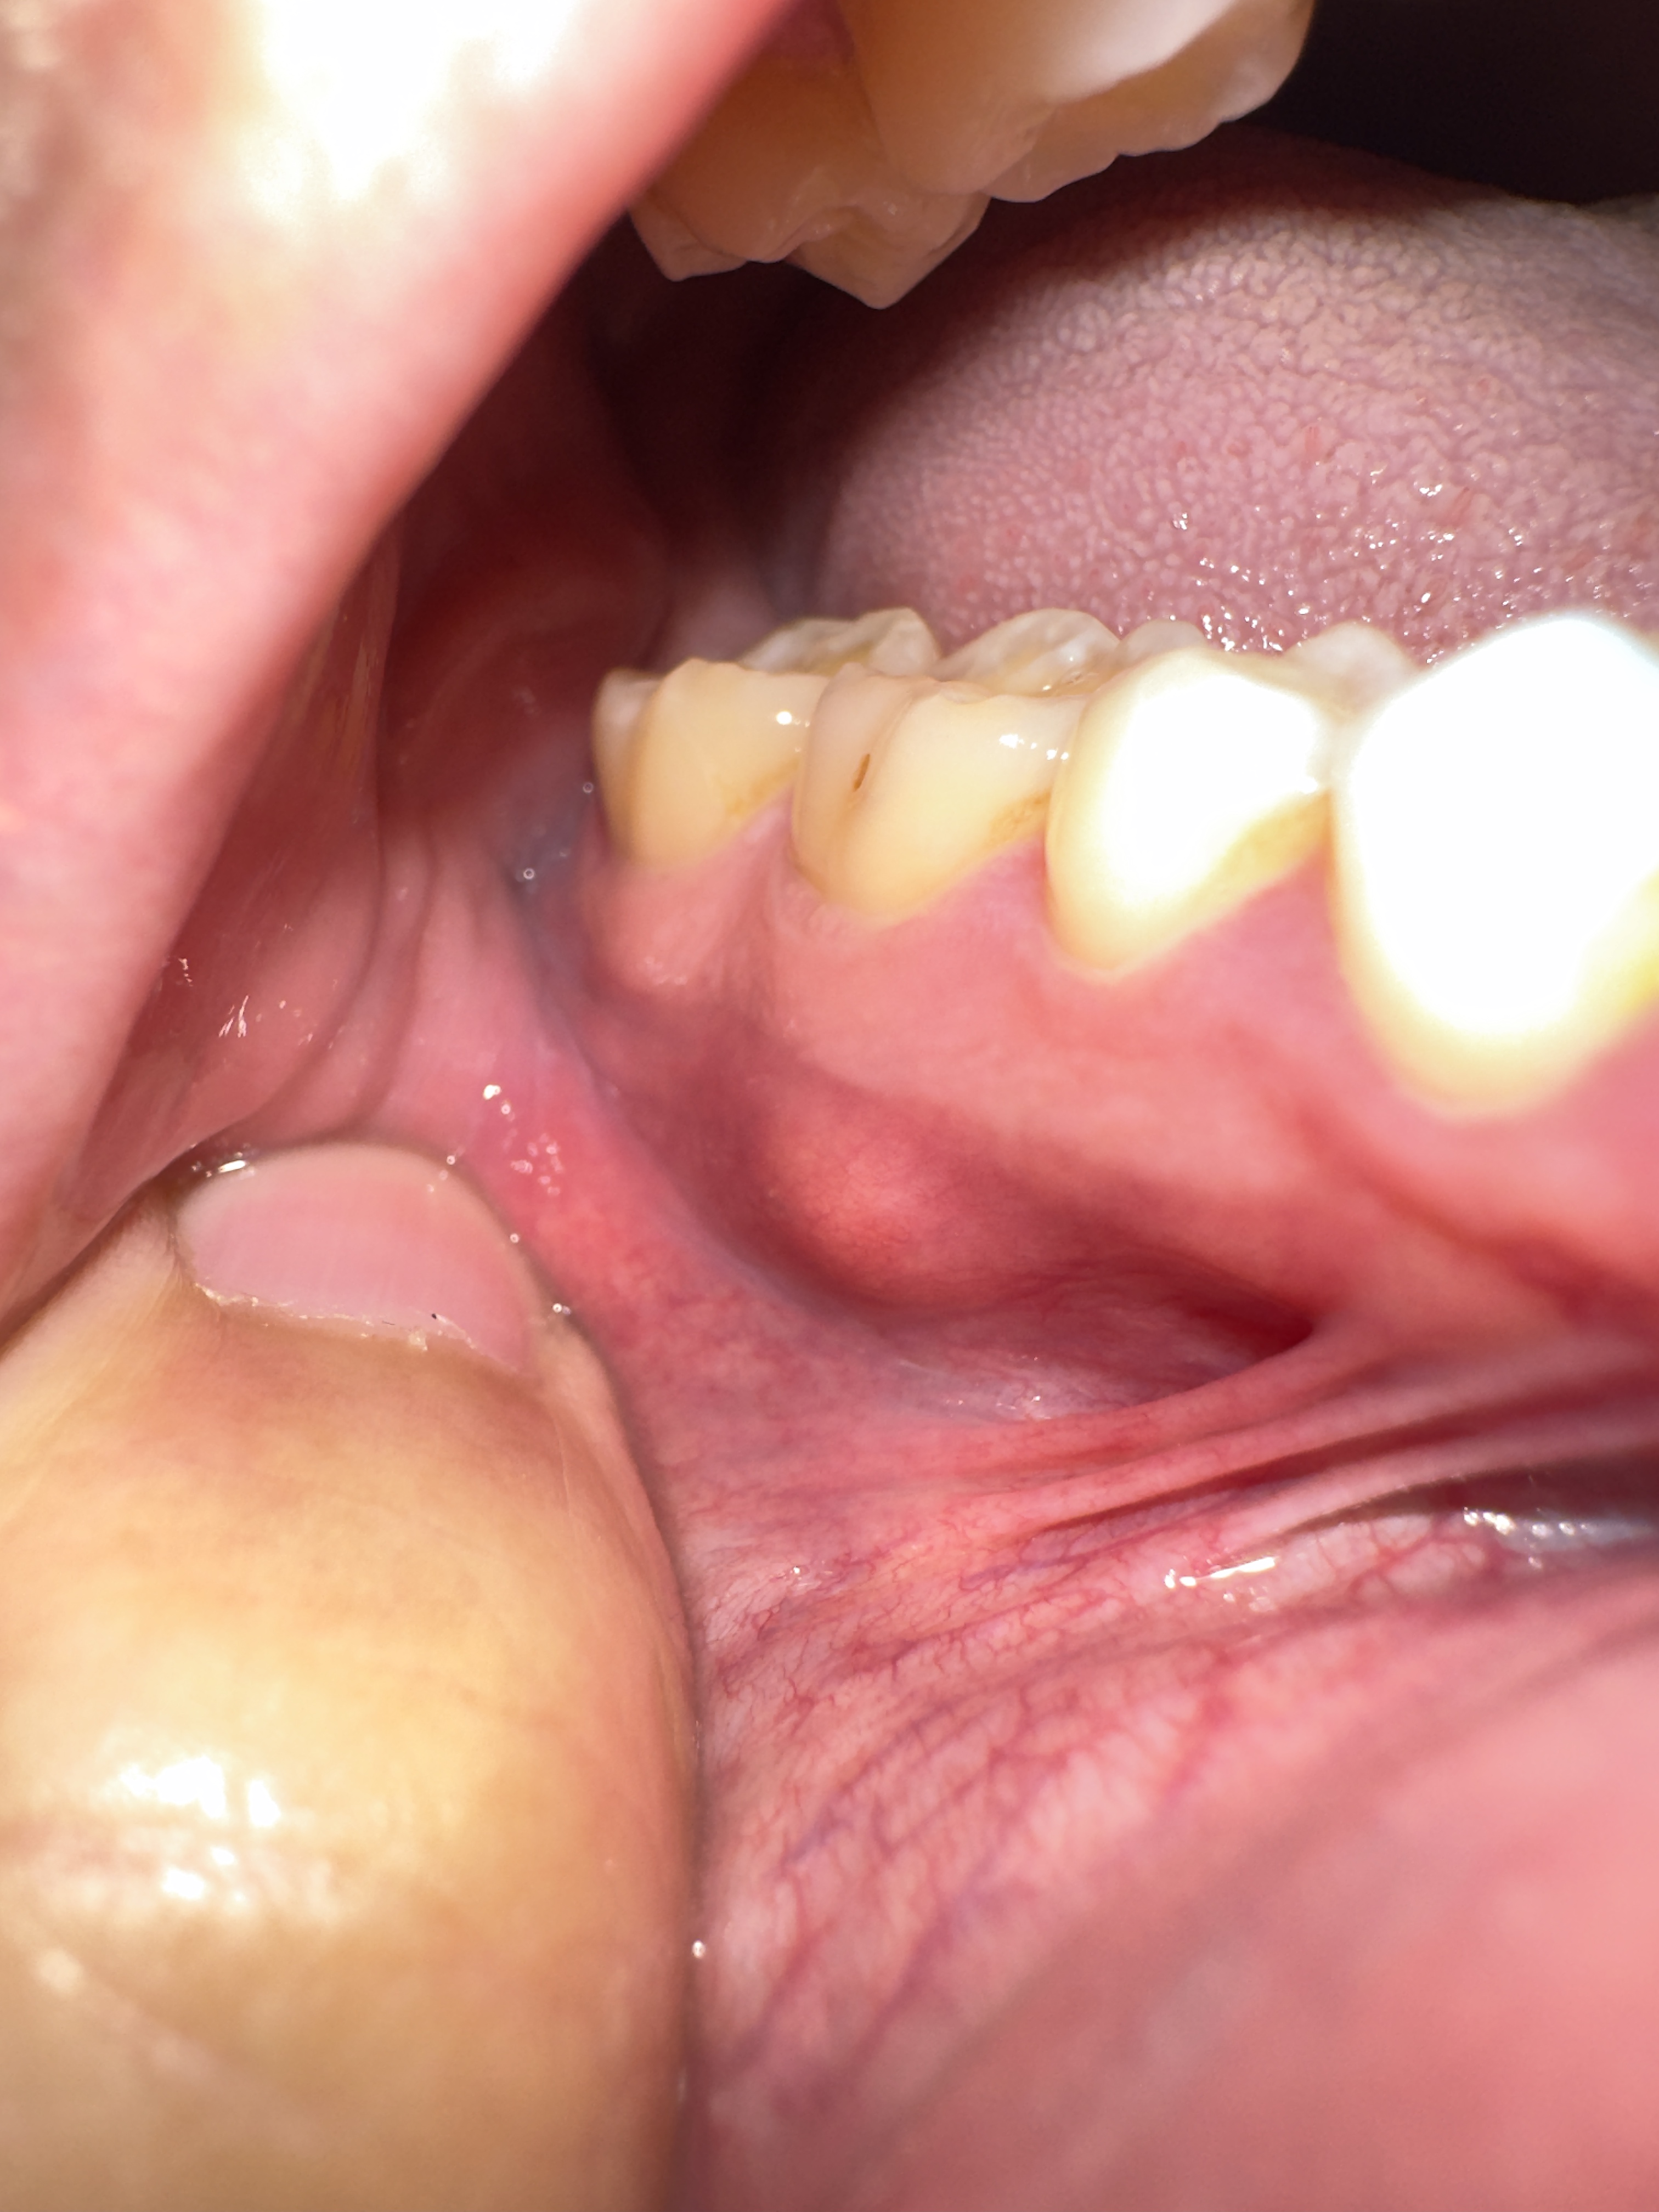

Hallo Tandarts Forum. Ik heb hard pijnloze bultje bij mijn tandvlees bij de kaak.. Ik vroeg mij af wat het kan zijn.. abces of cyste of onsteking..? zie ik meerendeels op internet voorbij komen. Ben al een hele lange tijd niet naar de tandarts geweest omdat ik nogal bang ben voor de tandarts, wat vroeger eigenlijk niet zo was.. Met vriendelijke groet!

Zou misschien een ontsteking kunnen zijn. Morgen gelijk bellen vooreen afspraak en een x-foto late make. Juist als je bang bent moet je naar de tandarts gaan om erge zaken, waaru juist bang voor bent, te voorkomen. Tegenwoordig hoef je helemaal niet bang te zijn. Verdoven en je voelt dat wj bezig zijn maar verder niets,